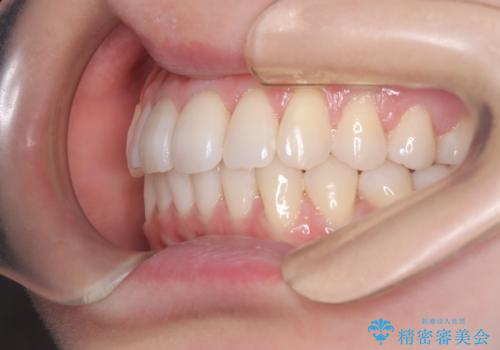

インビザラインモデレートによる前歯の叢生改善|IPR最小限で自然な歯並びへ

- 患者様は、**前歯の叢生(がたつき)**を気にされて来院されました。

できるだけ歯を削らずに、自然な歯並びを手に入れたいというご希望がありました。

診査の結果、中等度の叢生であったため、インビザラインモデレートでの対応が可能と判断しました。

歯へのダメージを抑えるため、IPR(歯間削合)は必要最小限にとどめる方針としました。

前歯の叢生は解消され、自然で調和の取れた歯並びが得られました。

「歯をほとんど削らずにきれいになった」と、患者様にもご満足いただけました。